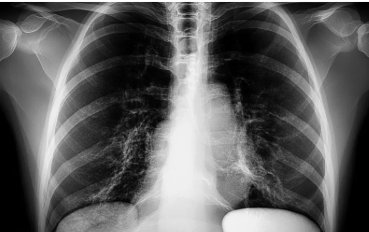

폐렴 증상 치료법

폐렴 증상이 의심되면 반드시 빠르게 병원을 찾아 진단을 받아야 합니다. 치료는 원인균, 환자의 건강 상태에 따라 달라지며, 아래와 같은 방법이 일반적으로 사용됩니다.

1. 항생제 치료

- 세균성 폐렴에는 페니실린, 세팔로스포린, 마크로라이드계 항생제가 주로 사용됩니다.

- 복용 기간은 평균 7-10일이며, 일부 장시간 작용하는 항생제는 35일로 단축되기도 합니다.

2. 항바이러스제 치료

- 바이러스성 폐렴은 바이러스 종류에 따라 적합한 항바이러스제를 사용하며, 인플루엔자 바이러스, RSV, 코로나바이러스 등 종류에 따라 치료제가 달라집니다.

3. 증상 완화 및 보조 치료

- 진해제·거담제: 기침 완화와 가래 배출을 돕습니다.

- 기관지 확장제: 숨쉬기 어려운 증상을 줄여줍니다.

- 진통제: 흉통 완화에 도움이 됩니다.

- 충분한 수분 섭취 및 휴식: 탈수를 막고 면역 기능을 높여줍니다.

- 구강 위생 관리: 감염 예방과 회복 촉진에 효과적입니다.

4. 입원 치료

- 중증 폐렴이나 기저질환이 있는 환자는 입원 치료가 필요하며, 산소 요법, 수액 치료, 전신 감시 등을 받을 수 있습니다.